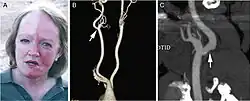

| A man exhibiting the asymmetric symptoms of Harlequin syndrome. One half of the forehead is more red than the other. | |

Harlequin syndrome, also known as "harlequin sign", is a condition characterized by asymmetric sweating and flushing on the upper thoracic region of the chest, neck and face. Harlequin syndrome is considered an injury to the autonomic nervous system (ANS). The ANS controls some of the body's natural processes such as sweating, skin flushing and pupil response to stimuli.[1] Individuals with this syndrome have an absence of sweat skin flushing unilaterally, usually on one side of the face, arms and chest. It is an autonomic disorder that may occur at any age.[2]